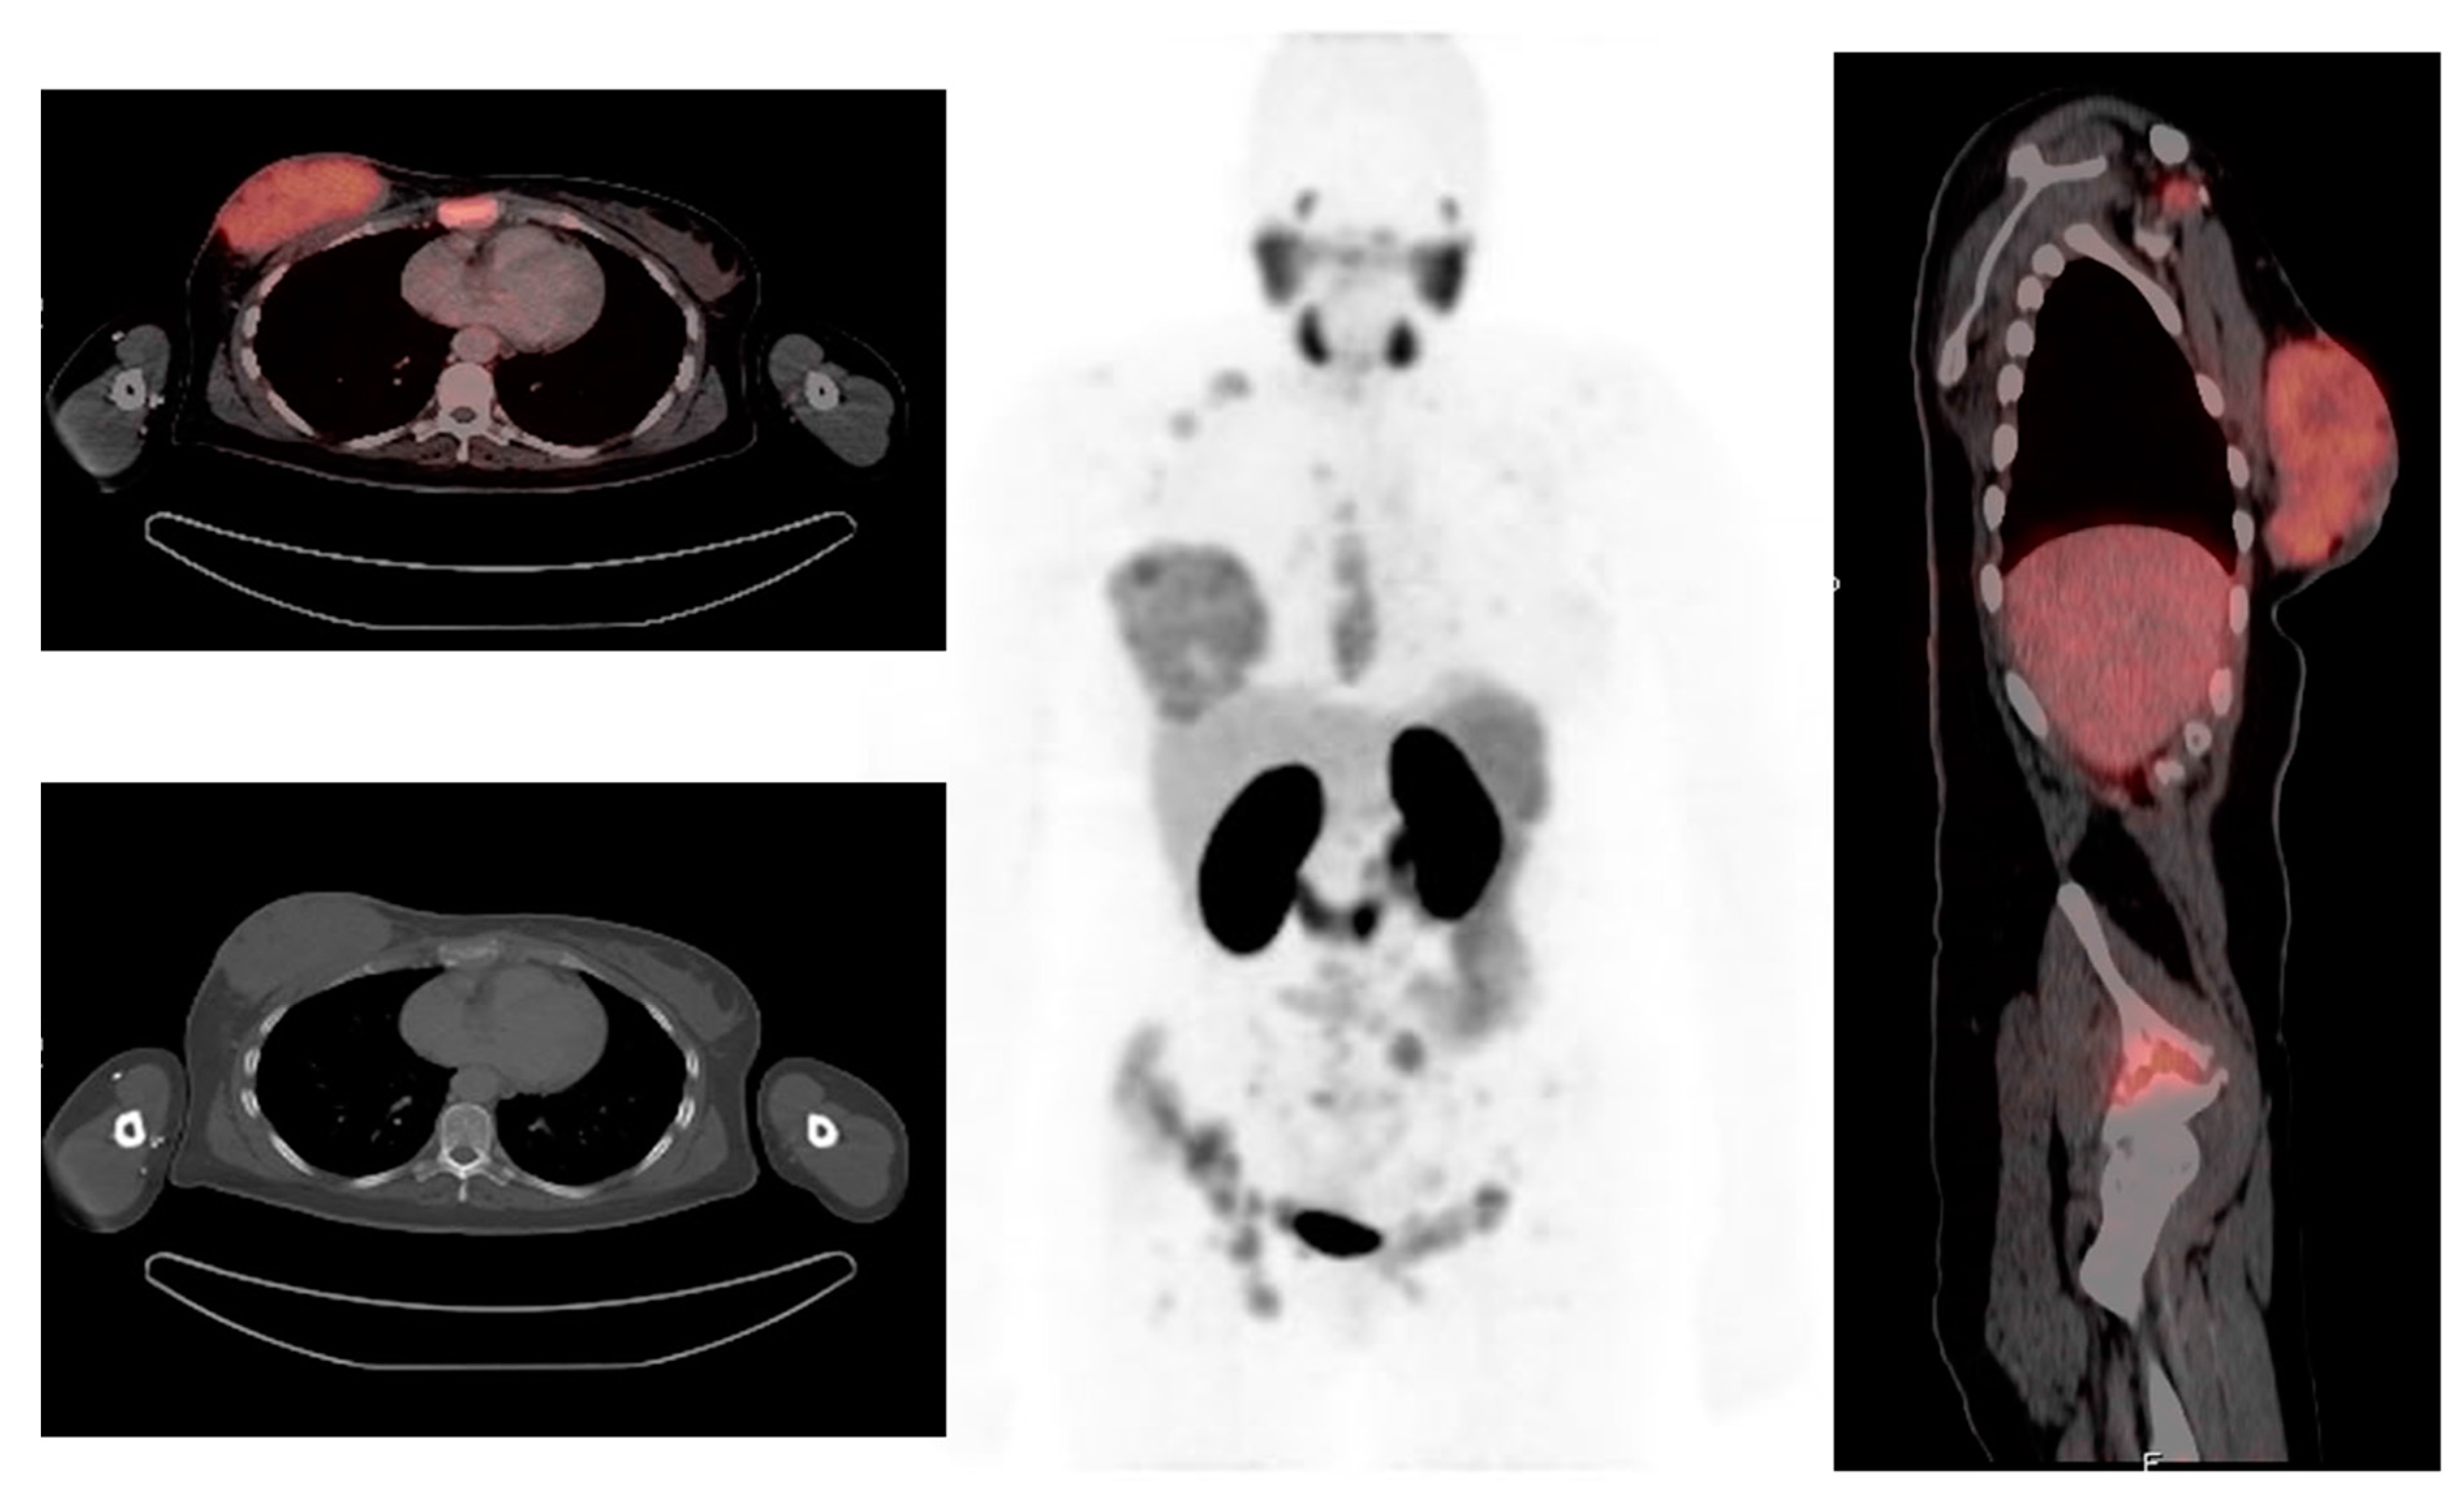

CXCR4 is a 7-transmembrane G-coupled receptor belonging to the chemokine receptor family and is expressed by various cells during development and thereafter [58]. Its main role in the hematopoietic system is to control stem cell retention and the homing of hematopoietic cells to the bone marrow and lymphoid organs [49]. CXCR4 is frequently overexpressed in invasive breast cancer and has an important role in tumor migration, invasiveness, metastasis, and proliferation [59]. Vag et al. evaluated 18 patients with breast ca who underwent 68Ga-Pentixafor PET/CT or PET/MR, 13 of the patients had a first diagnosis of breast cancer, 4 patients had recurrent disease after primary breast cancer, and 1 patient with axillary lymph node metastasis of unknown primary [60]. Sixty nine percent (9/13) of the primary tumors were visually detected with 68Ga-Pentixafor, and all 5 metastases could be visually identified. Eight patients (4 recurrent breast cancer patients and 4 primary breast cancer patients) received 18F FDG-PET within 2 weeks after administration of 68Ga-Pentixafor. It was noted that a higher SUVmax of 18F-FDG was observed in all cases, compared with 68Ga-Pentixafor. It was also noted that the uptake seen in breast cancer is associated with a poorer prognosis [60]. Higher CXCR4 expression is seen in triple-negative breast cancer compared to the luminal subtypes, as demonstrated in Figure 4. 68Ga-Pentixafor PET/CT may have a role in prognostication of breast cancer patients and in selecting potential candidates for therapies targeting CXCR4.

Figure 4.

A 74-year-old female with triple-negative breast cancer underwent 68Ga-Pentixafor PET/CT. The images demonstrate inhomogeneous CXCR4 receptor expression in the primary lesion in the right breast as well as right axillary lymph nodes.